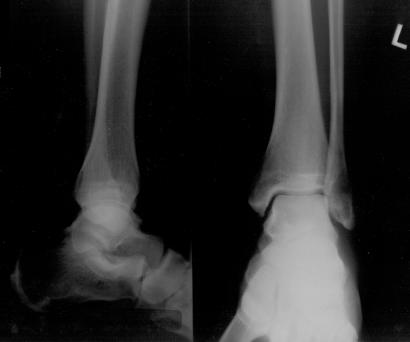

Pre-corrective surgery X-Rays of the damaged right & left legs / ankles

These x-rays were taken at Dr Armendariz’s office, just prior to performing any corrective surgery. As can be seen in these images,

there was no tibia bracing provided by Dr. Keller. Liam was released from Dr Keller’s care with instructions that full weight bearing could

be accomplished within 2 months of Keller’s last surgical procedure. The best example to examine is the second image (from the left) of the

top how. Notice how the bones that should be aligned with the tibia are in fact on the other side of the leg. The third image shows how badly

Liam’s left foot was twisted as a result of the pool placement of the external fixation. What is not obvious is that the screw at the bottom

of the plate on the right fibula missed being screwed into the plate.